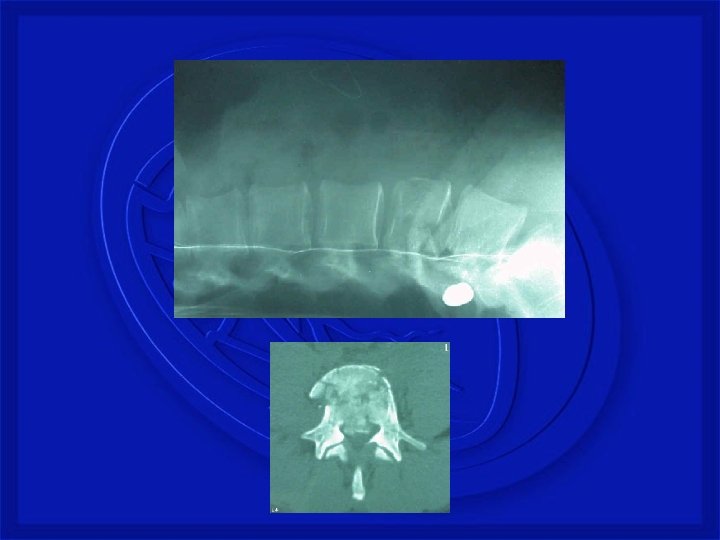

• TRAUMA FECHADO • Fratura cervical • Angulação aguda do pescoço por flexão e extensão violenta. • Acidente automobilístico e mergulho

• TRAUMA FECHADO • Fratura Torácica • Rara devido proteção de caixa torácica • Tóraco Lombar • Comum. Quedas com impacto dos pés e região glútea • Lombar baixa • Os traumas produzem ruptura de discos

Registro fotográfico Pessoal